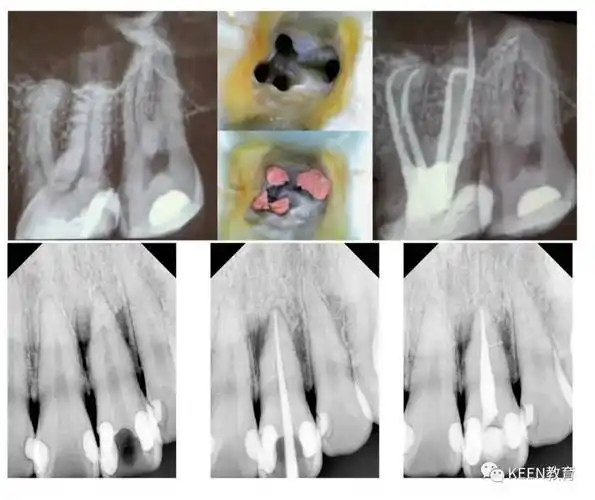

向下滑动查看课程大纲备注:自带离体牙数颗(前牙,前磨牙,磨牙)11.